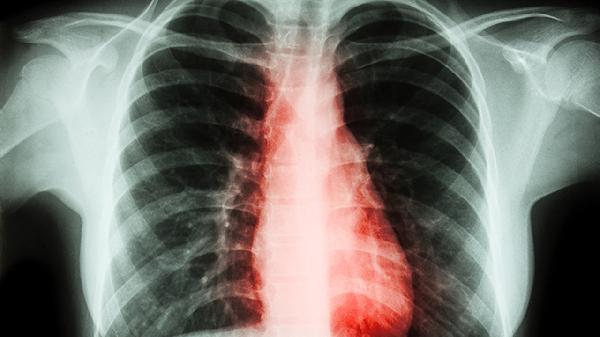

1、胸背部疼痛

胸椎神经根受压常引发沿肋间神经分布的放射性疼痛,疼痛可呈束带样向胸腹部扩散,咳嗽或体位变动时加重。椎间盘源性疼痛多表现为慢性钝痛,而肿瘤或骨折导致的疼痛常为突发锐痛。急性期可遵医嘱使用塞来昔布胶囊、双氯芬酸钠缓释片等非甾体抗炎药,配合胸椎牵引缓解症状。